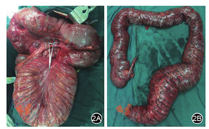

患者男性,46岁,因"反复腹胀腹痛伴排便不畅1个月,加重伴呕吐3天"于2017年7月20日急诊入院。患者于1个月前因腹胀腹痛伴排便不畅于外院就诊,予以导泻、灌肠等处理症状好转,后患者仍间断出现腹胀伴腹痛,均于外院对症治疗,3天前患者腹痛腹胀症状较前加重并恶心呕吐,查腹部立位平片示:肠梗阻。外院予保守治疗3天后症状无缓解,遂急诊转至苏州大学附属第一医院。患者主诉患有"便秘"数年,自服泻药均可通便,无其他特殊药物服用史,近期工作劳累,精神压力较大,否认毒物、放射性物质接触史,无外伤手术史。入院查体:急性痛苦面容,全腹膨隆,未见胃肠型及蠕动波,全腹压痛明显,有反跳痛、肌紧张,腹部叩诊鼓音,移动性浊音(-),肠鸣音弱,1~2 b/m。直肠指检:胸膝位,肛门无痔块脱出,无肛裂,指检未及肿块,指套无染血。腹部CT(平扫+增强):全结肠普遍扩张,乙状结肠高密度影,考虑粪便(图1)。以"巨结肠伴梗阻、急性腹膜炎"收治入院,急诊行剖腹探查术。术中见:腹腔中等量清亮腹腔积液,空肠无扩张,回肠稍扩张,升结肠、横结肠、降结肠以及乙状结肠明显扩张、冗长,最大直径约15 cm,其中以乙状结肠扩张尤为严重(图2),结肠内充满干结大便,质硬,术中行直肠指诊未触及肿块。遂行结肠次全切除术+末端回肠造口术。术后病理:(次全结肠)肠壁黏膜慢性炎,肌壁间可见神经元,浆膜面局灶见中性粒细胞浸润,部分血管充血,阑尾慢性炎(图3)。患者术后4天半流质饮食,术后10天出院。术后2个月随访,患者体重较前增加10 kg。于2017年10月31日行"造口回纳(回肠直肠吻合术)"。患者回肠直肠吻合术后出现腹泻症状,经药物治疗后,每天排便可控制在3次以内。